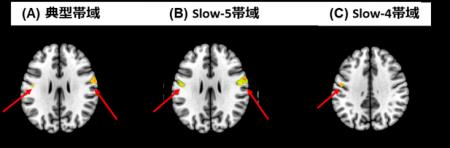

安静時機能的MRI解析の結果、SAD患者は、「典型帯域(図1A)」および「slow-5帯域(図1B)」では、身体の感覚情報を統合する領域「体性感覚野」の一部である「両側中心後回(PostCG)」において、HC群よりも有意に低い脳活動(mfALFF)が認められ、「slow-4帯域(図1C)」では左中心後回に低下がみられました。

図1. 社交不安症患者で低下したmfALFF(周波数別) カラーバーが赤いほどmfALFFの低下が強い。赤矢印部分が中心後回を示す。

これらのmfALFF値と臨床指標との間には有意な相関は認められませんでしたが、認知機能との相関解析では、slow-5帯域においてSAD群の左中心後回のmfALFFが低いほど、すなわち脳のこの部位の自発的活動が低いほど、与えられた課題に対する答えを最初に選択するまでの反応時間が長い、という有意な負の相関があることが認められました。これらの結果から、SAD患者では中心後回を中心とする周波数依存性の自発的脳活動の低下が認められ、認知機能との関連も周波数依存性があることが示唆されました。